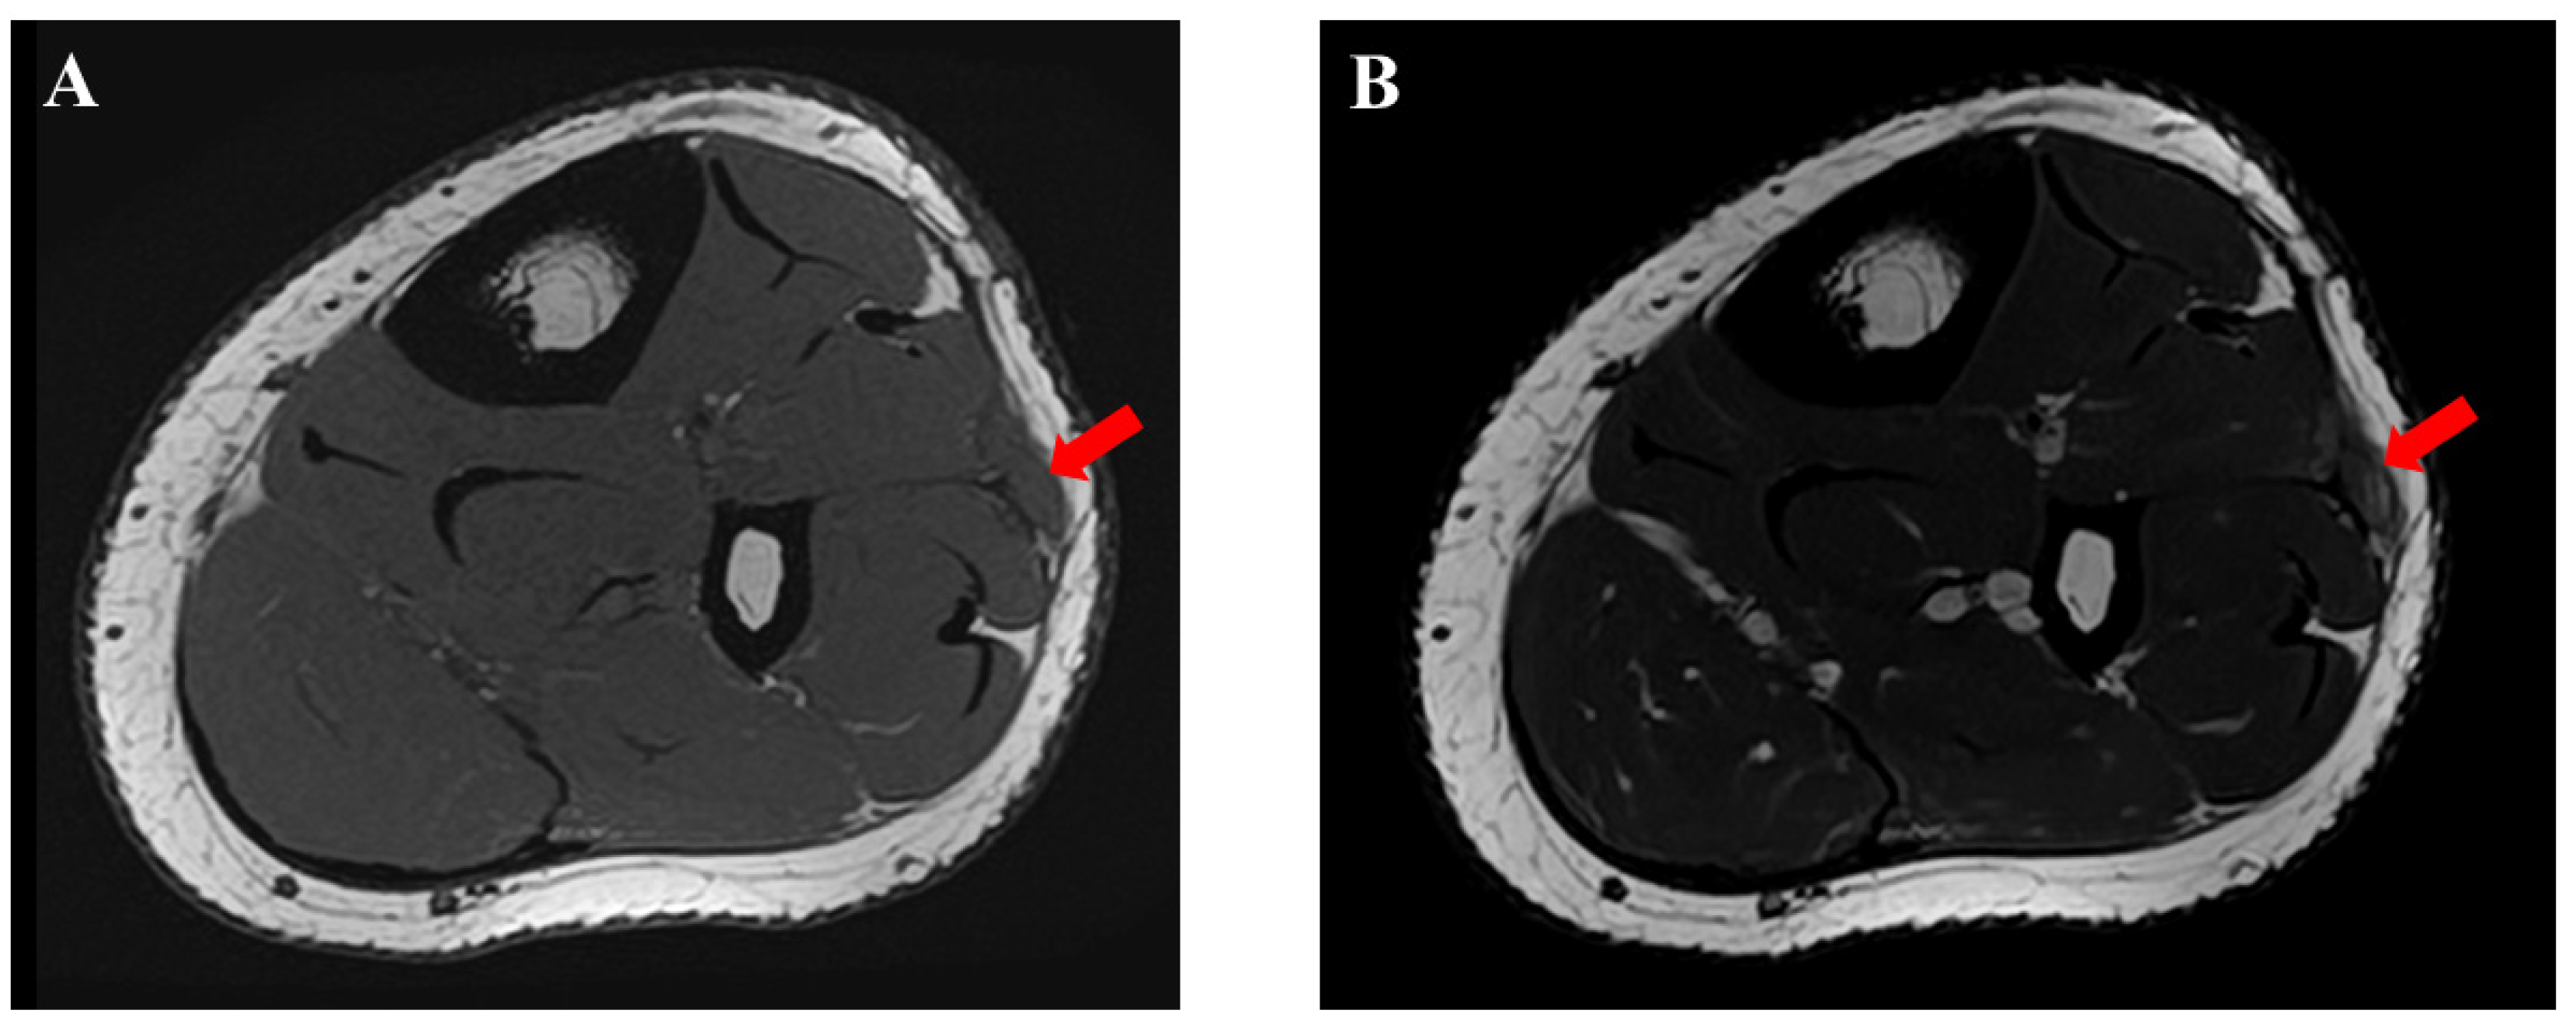

Postoperatively, the ankles were not immobilized, and weight bearing was allowed as tolerated. Ankle range-of-motion exercises were initiated immediately after surgery. Several days after surgery, he presented with paresthesia and impaired touch sensation over the dorsal area of the left foot. At the three-month follow-up, a swelling lesion with hard elasticity was identified between the middle and the most distal surgical wounds. The lesion did not disappear with the patient in the supine position. On palpating this lesion, he recognized a radiating sensation over the left dorsal foot supplied by the SPN. An ultrasonographic examination showed an isolated lesion (8.0 × 12.0 mm) (Figure 5). MRI showed a lesion that was iso-signal on T1-weighted images and high signal on T2-weighted images (Figure 6). Traumatic neuroma of the SPN was considered. While the lesion did not disappear, he returned to playing baseball six months after surgery. At the 24-month follow-up examination, recurrent TAMHs were not found in the bilateral lower extremities. The patient was asymptomatic without palpation of the lesion and did not demand surgical intervention for this lesion.

Figure 6. Postoperative magnetic resonance imaging (MRI) findings of the traumatic neuroma of the superficial peroneal nerve (red arrow). (A) T1-weighted image. (B) T2-weighted image.